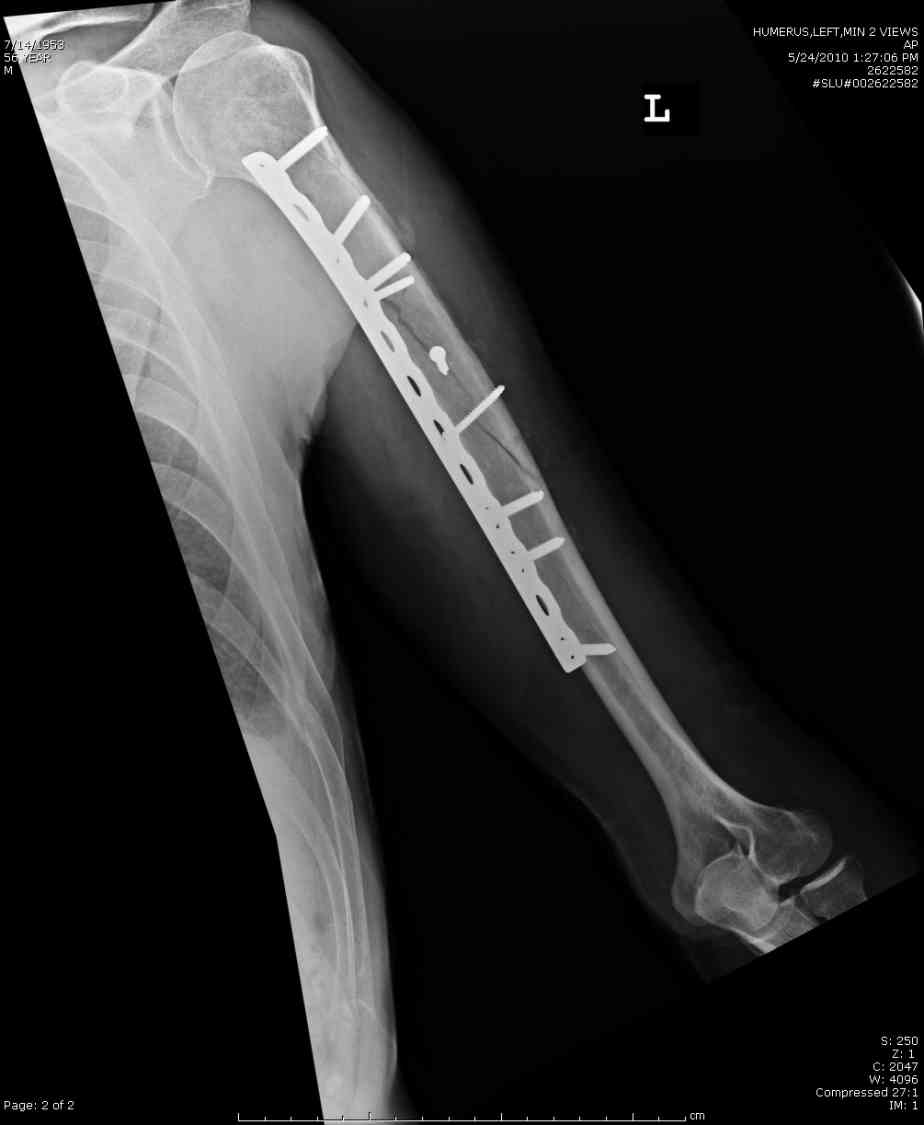

Кроме интрамедуллярного остеосинтеза, имеются другие варианты фиксации, наружный фиксатор и например здесь перелом плеча с повреждением нерва леченный открытым методом. Применен задний доступ с инспекцией нерва, межфрагментарная компрессия, фиксация узкой пластиной 4.5 мм.

Уважаемый Александр Николаевич! На продемонстрированных вами рентгенограммах имеется достаточно большое на мой взгляд смещение отломков после фиксации блокируемым гвоздем. На счет полной функции все понятно, а нет ли каких либо сосудистых расстройств конечности? Имею ввиду венозную недостаточность или лимфостаз.